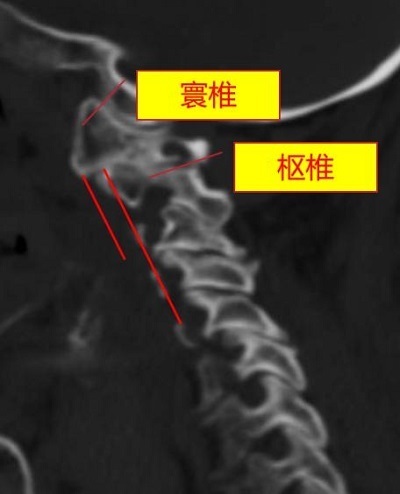

术前,颈椎CT表示寰枢椎脱位(频频为寰椎、枢椎在合并水平线)。重庆市东谈主民病院(重庆大学从属东谈主民病院)供图